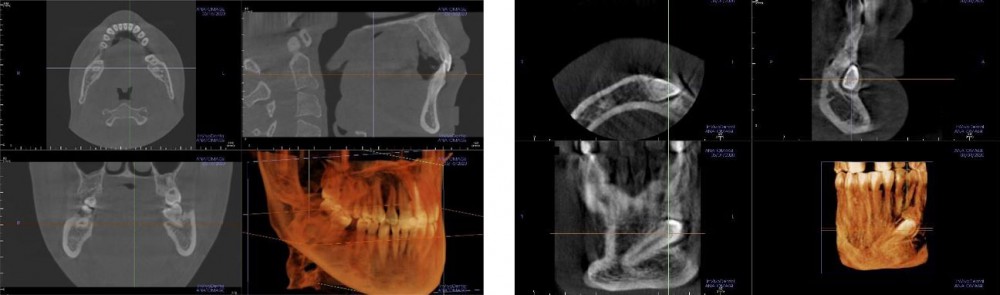

W styczniu wyposażyliśmy naszą pracownię w nowy tomograf komputerowy Orthopantomograph 3D Pro firmy Kavo. Jest on następcą wcześniej stosowanego przez nas aparatu Orthopantomograph OP 200 fińskiej firmy Instrumentarium. Warto wspomnieć, że jako pierwszy gabinet ortodontyczny w województwie opolskim stworzyliśmy w 1997 roku własną pracownię rtg, dla wygody naszej i oczywiście naszych pacjentów. Od wielu już lat, analogowy jeszcze wówczas aparat do zdjęć pantomograficznych z przystawką do cefalomoetrii włoskiej produkcji, jest jednym z eksponatów największego na świecie Muzeum Lamp Rentgenowskich znajdującego się na Politechnice Opolskiej.

Jest to uniwersalny tomograf z innowacyjna technologią niskiej dawki Low Dose Technology, automatyczną kontrolą dawki. Jest to szczególnie istotne przy wykonywaniu zdjęć kontrolnych u dzieci.

Aparat ten pozwala na uzyskanie precyzyjnych obrazów 2D dzięki funkcji multilayer i technologii wiązki RTG w kształcie litery V. Badanie może być wykonane w 4 rozdzielczościach obrazu w trybie 3D. Posiada funkcję redukcji artefaktów z metalowych elementów. Ma również 5 wielkości pól obrazowania.

Dla wszystkich pięciu pól obrazowania można wybrać jeden z trzech trybów rozdzielczości. Dla skanu 5/5 dodatkowo dostępny jest też tryb Endo.